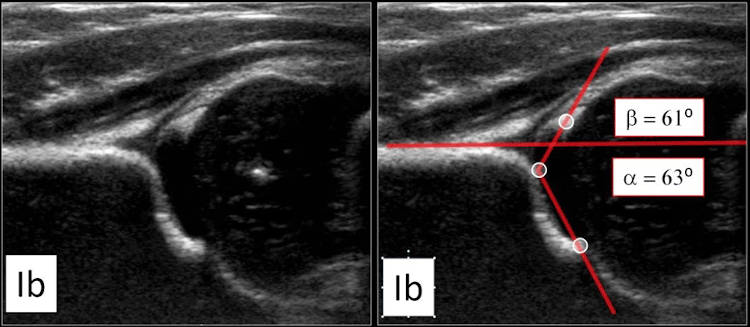

όπως και λογισμικό για έλεγχο δυσπλαστικού ισχίου στα νεογνά (μπορούμε να εξετάσουμε την επικέντρωση της μηριαίας κεφαλής στη κοτύλη, την λοξότητα της κοτύλης και την σταθερότητα της αρθρώσης με τον δυναμικό υπέρηχο σε ειδικό κρεβατάκι)